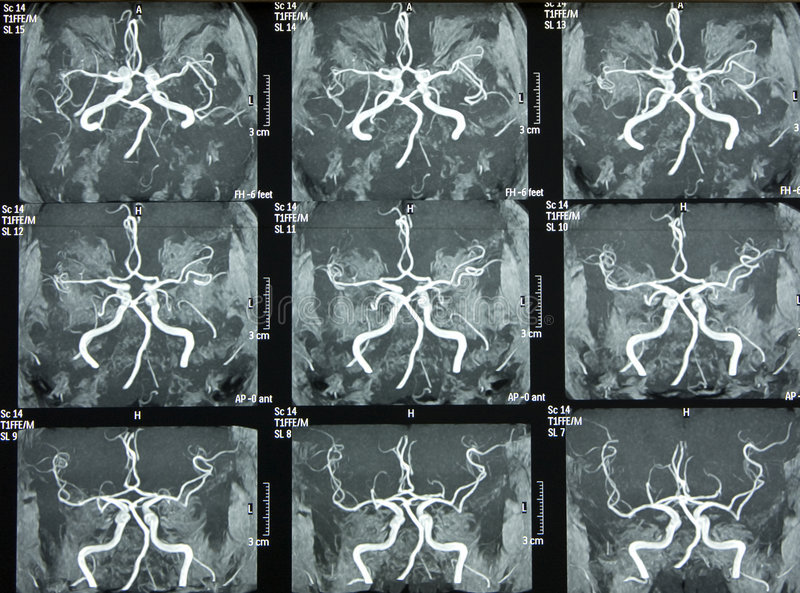

脑卒中磁共振筛查

专为老年人群提供精准的脑卒中早期预警解决方案,应用3D TOF MRA等全新的无损伤性血管成像技术,更清晰显示远端及细小血管,无需注入对比剂,更适用于早期脑血管病变预防与诊断。应用联影光梭3.0T磁共振特有的uCS-DWI序列,是急性脑梗死最敏感的序列

超早期卒中预警:DWI序列能在发病数分钟内显示急性梗死灶,实现超早期诊断;SWI序列可敏锐发现常规扫描难以显示的微出血灶,为血管风险评估提供关键依据。

脑血管系统全景评估:MRA无需造影剂即可清晰显示颅内主要动脉的形态、狭窄或闭塞情况,结合SWI对微小血管病的评估,实现从大血管到微血管的综合筛查。

脑结构与病变精准分析:一站式全面评估脑实质、脑室系统及病灶。对脑梗死分期、脑肿瘤鉴别、脑出血演变、动静脉畸形、颅内血肿等具有重要诊断价值,为治疗方案选择与预后判断提供全面影像学依据。